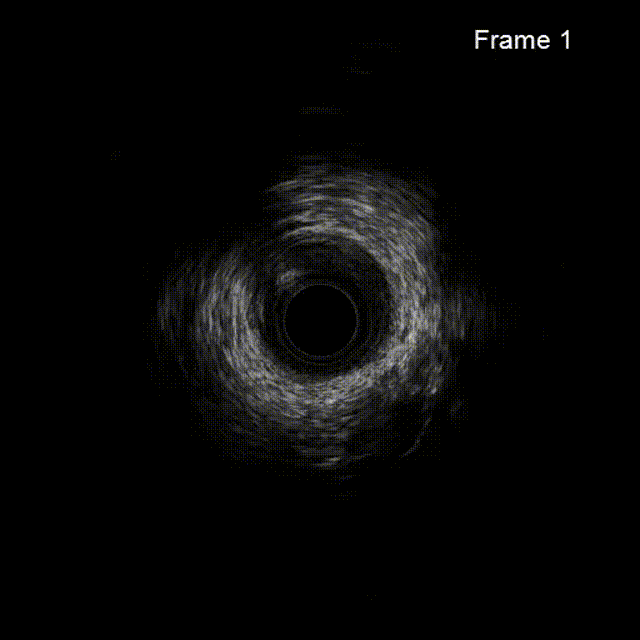

IVUS导管可置于LCX内指导LAD开口位置,闭塞段开通后可应用IVUS检查关注导管是否在真腔、有无夹层血肿等。

依次用Pinoeer 2.0mm x 15mm、Pinoeer 2.5mm x 15mm球囊至病变处反复扩张,送入Marvel导丝至D1远段做保护,LAD行IVUS检查。

IVUS检查示:可见导丝全程走行与血管真腔,近中段重度纤维增生斑块伴局部钙化,远段血管床废用性萎缩。

术后行IVUS检查示:支架定位贴壁扩张良好,LAD开口MSA:7.43mm2。